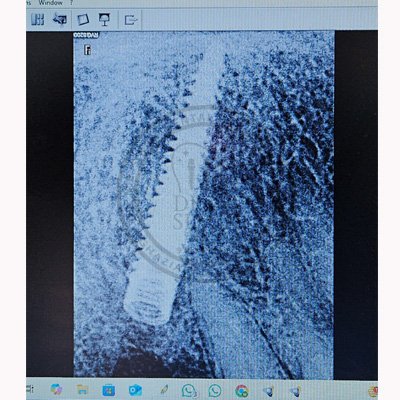

Case – 11 Baleram